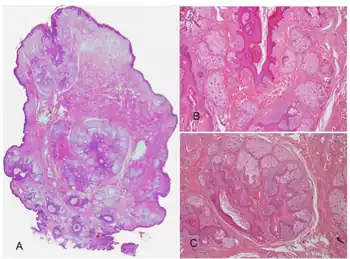

Dermatoscopy - folliculosebaceous cystic hamartoma, a)exophytic lesion, b)mature sebaceous lobules, c) stroma is prominent, with fibrillar bundles of collagen